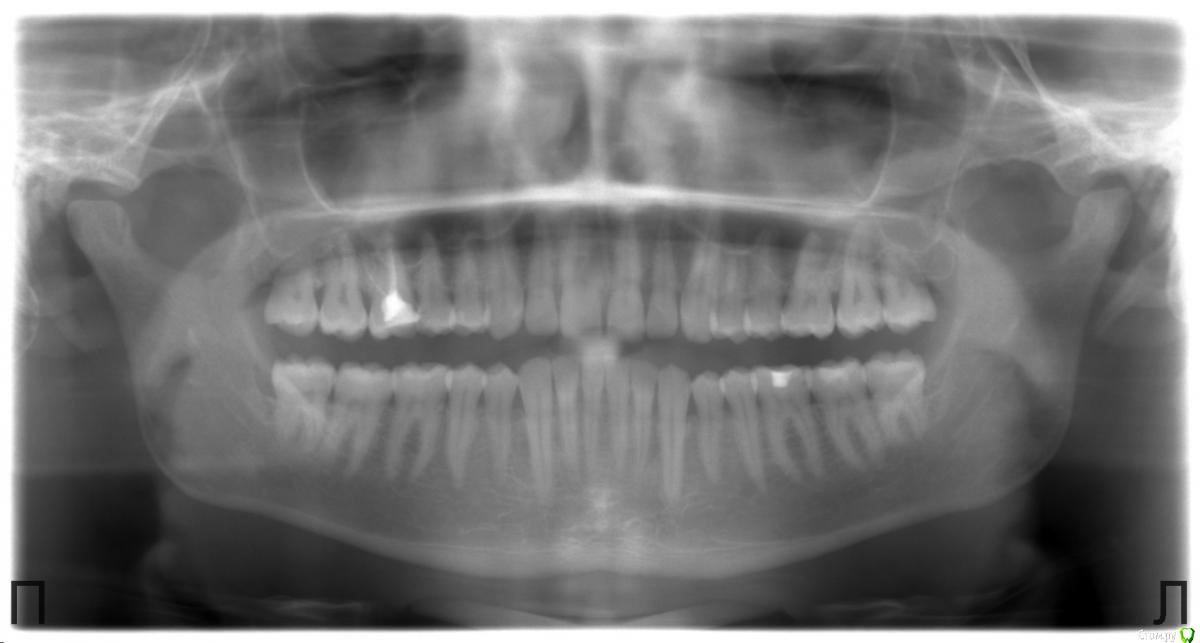

Есть 2 снимка ОПТГ - май 2013 года и май 2017 года. Видно изменения за 4 года.

2017:

post-34691-0-04376400-1495615342_thumb.jpg

1. Подскажите, пожалуйста, есть ли необходимость в лечении зубов вообще по челюстям (есть снимки).

2. И что делать конкретно с зубом "16", над которым я уже 5 лет в раздумье.

Когда-то очень давно я его пролечивал с каналами и пломбированием. Спустя лет 15-20 имею в нём картину, требующую лечения с протезированием.